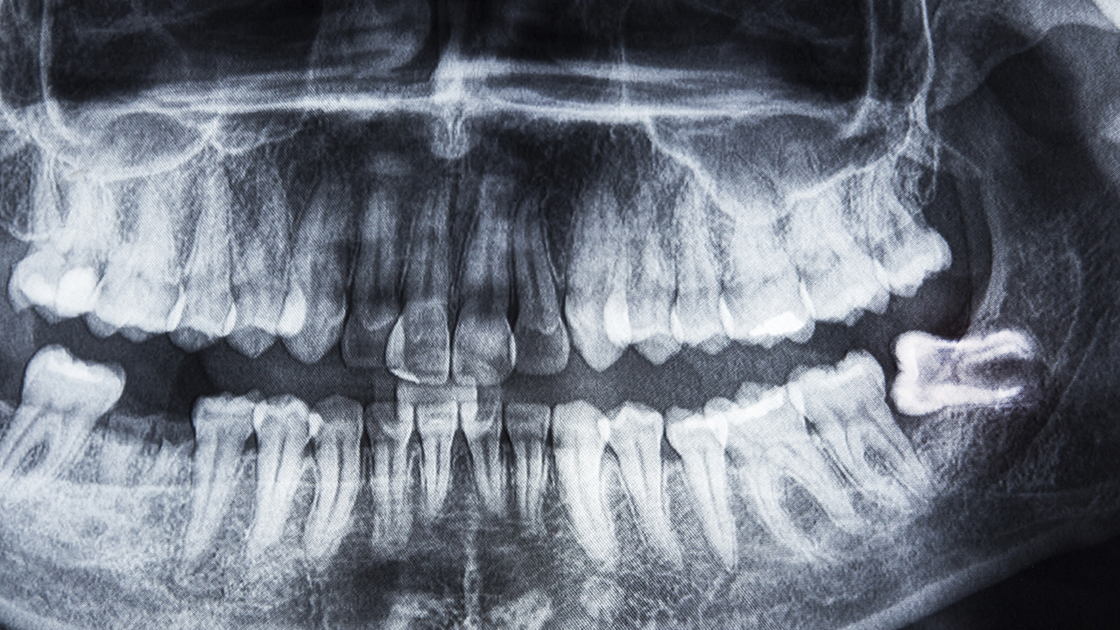

Wisdom Tooth Removal (3rd Molars)

When assessing whether wisdom teeth should be removed, we take the following factors into account: jaw size, crowding, proper occlusion, and impaction.